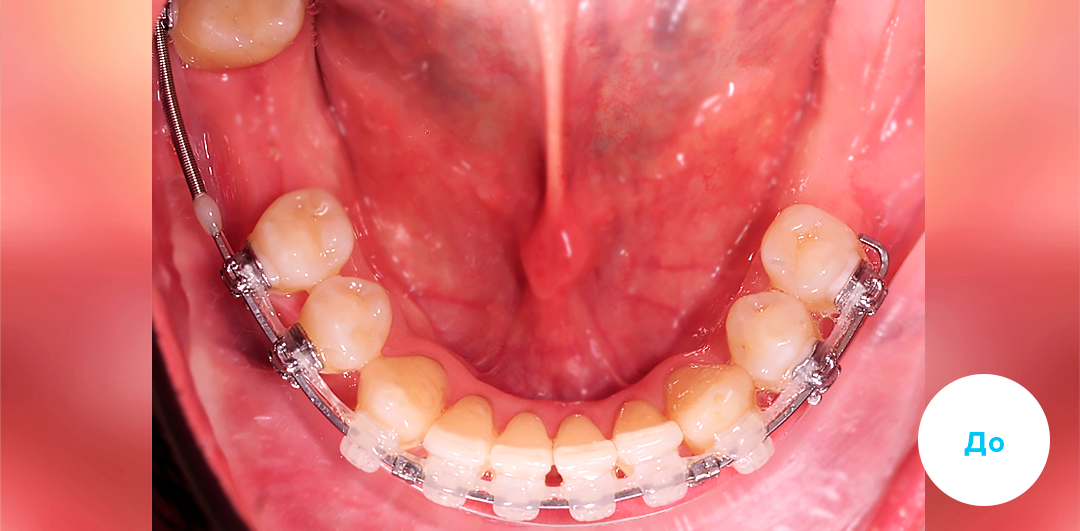

Результаты лечения